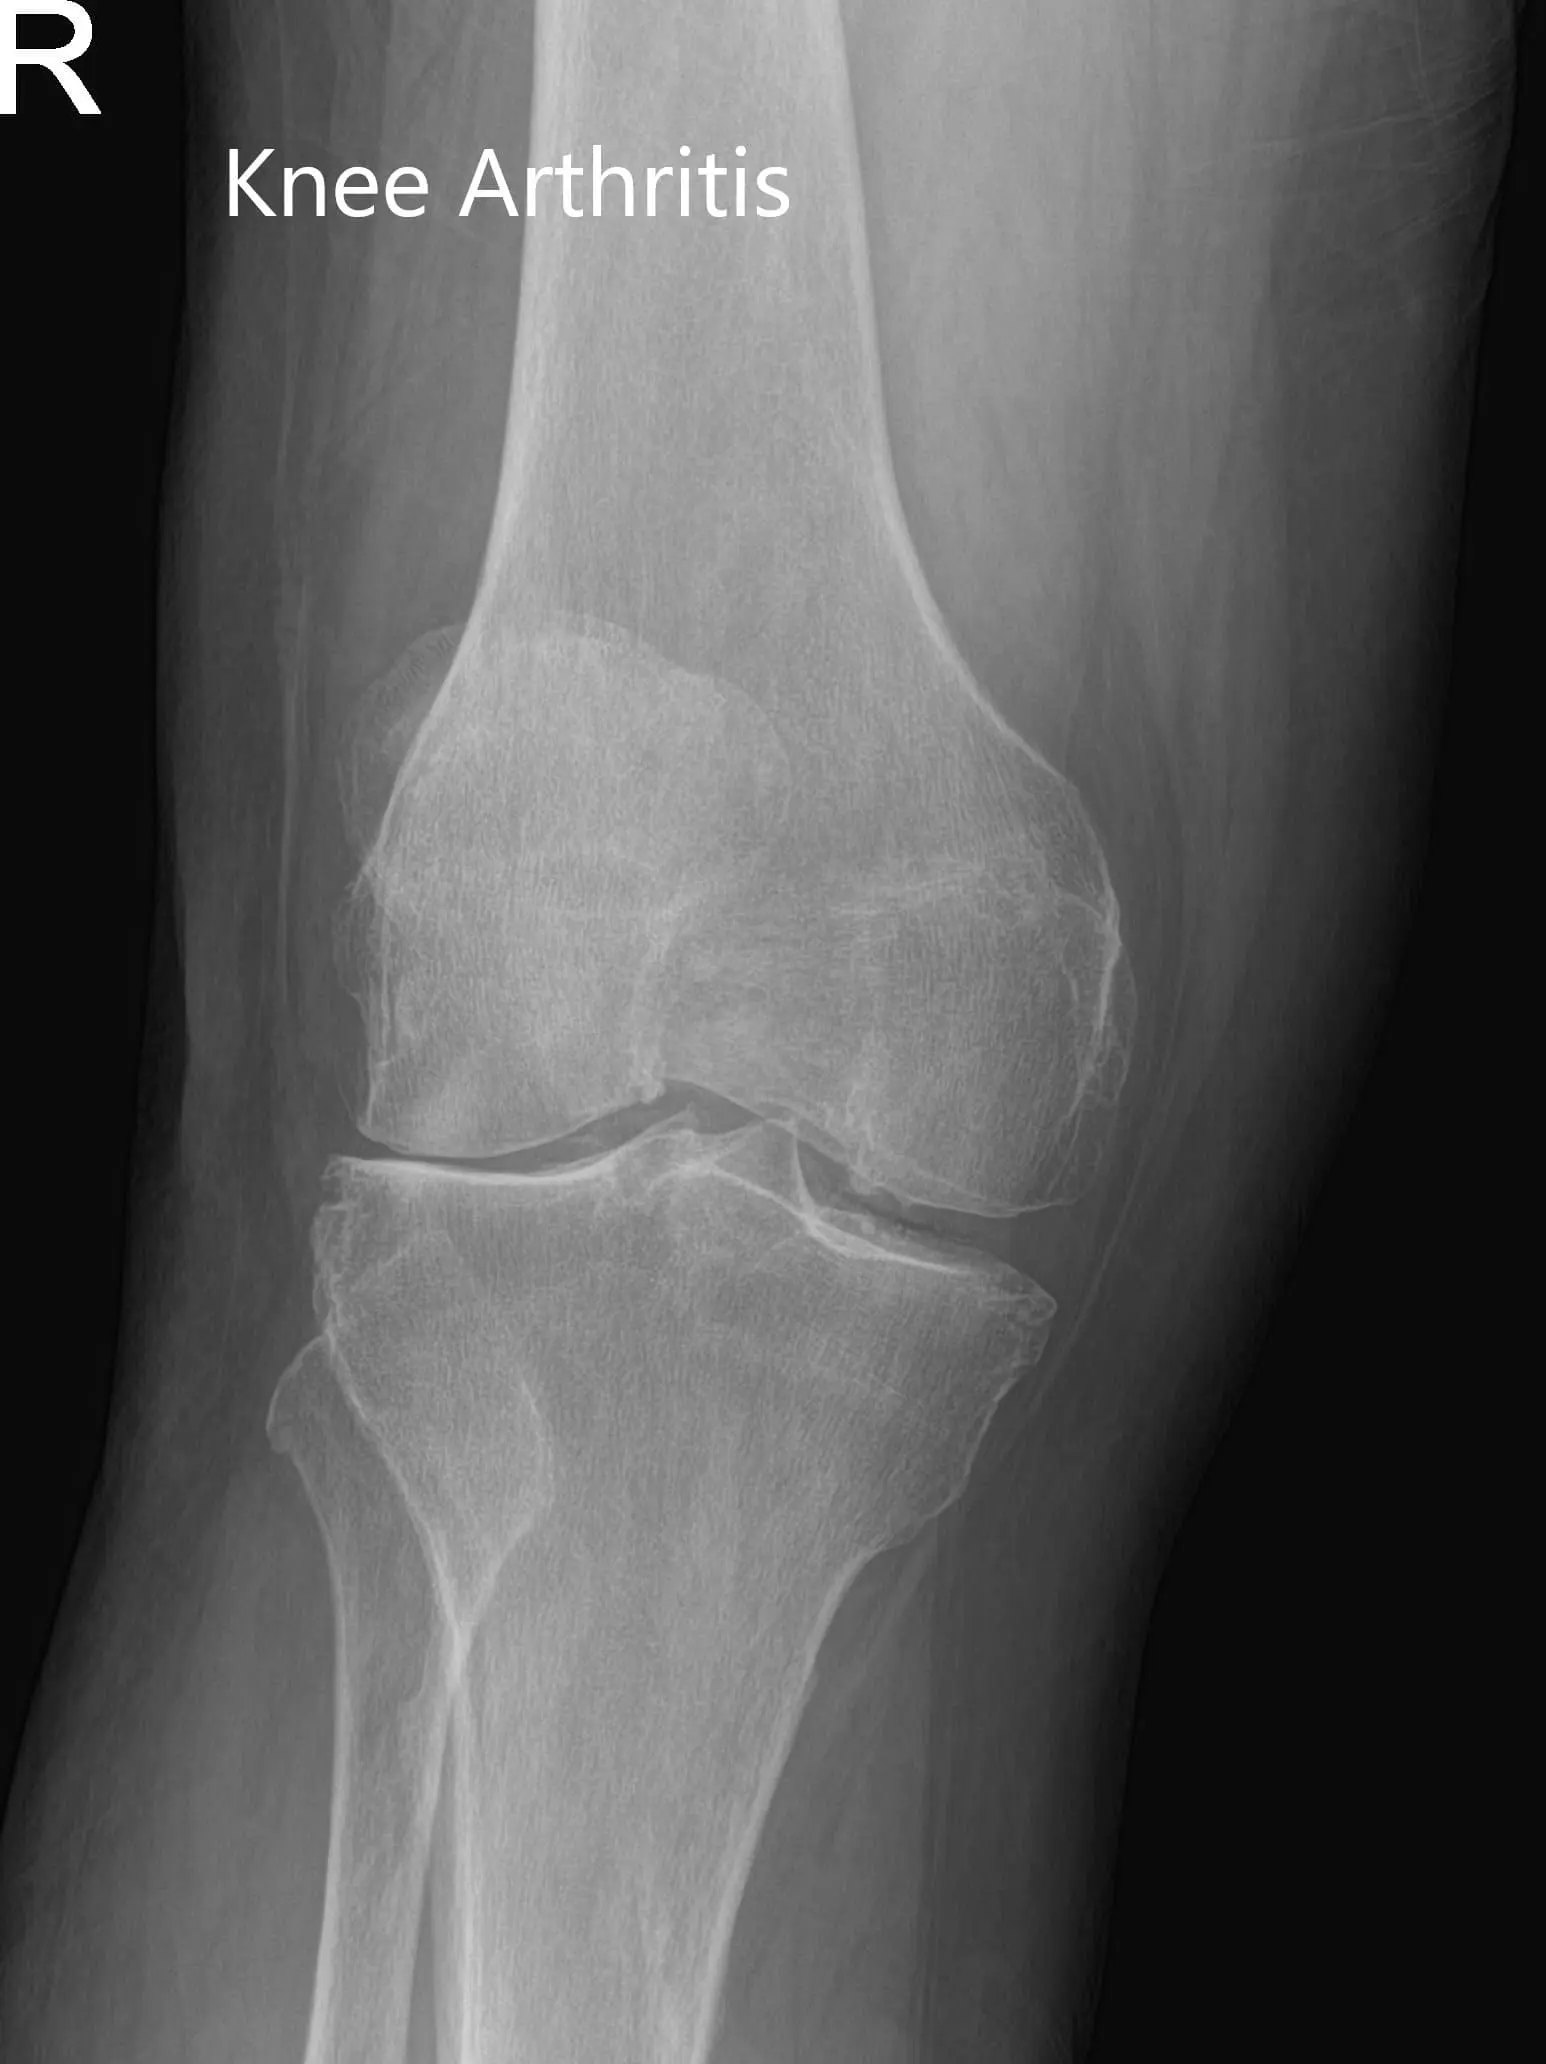

Imaging studies revealed severe bilateral knee arthritis. The right knee was worse than the left side. She was advised right total knee replacement with custom instruments. Risks, benefits, and alternatives were discussed at length with her. She agreed with the plan.

X-ray of the right knee in anteroposterior and lateral views.